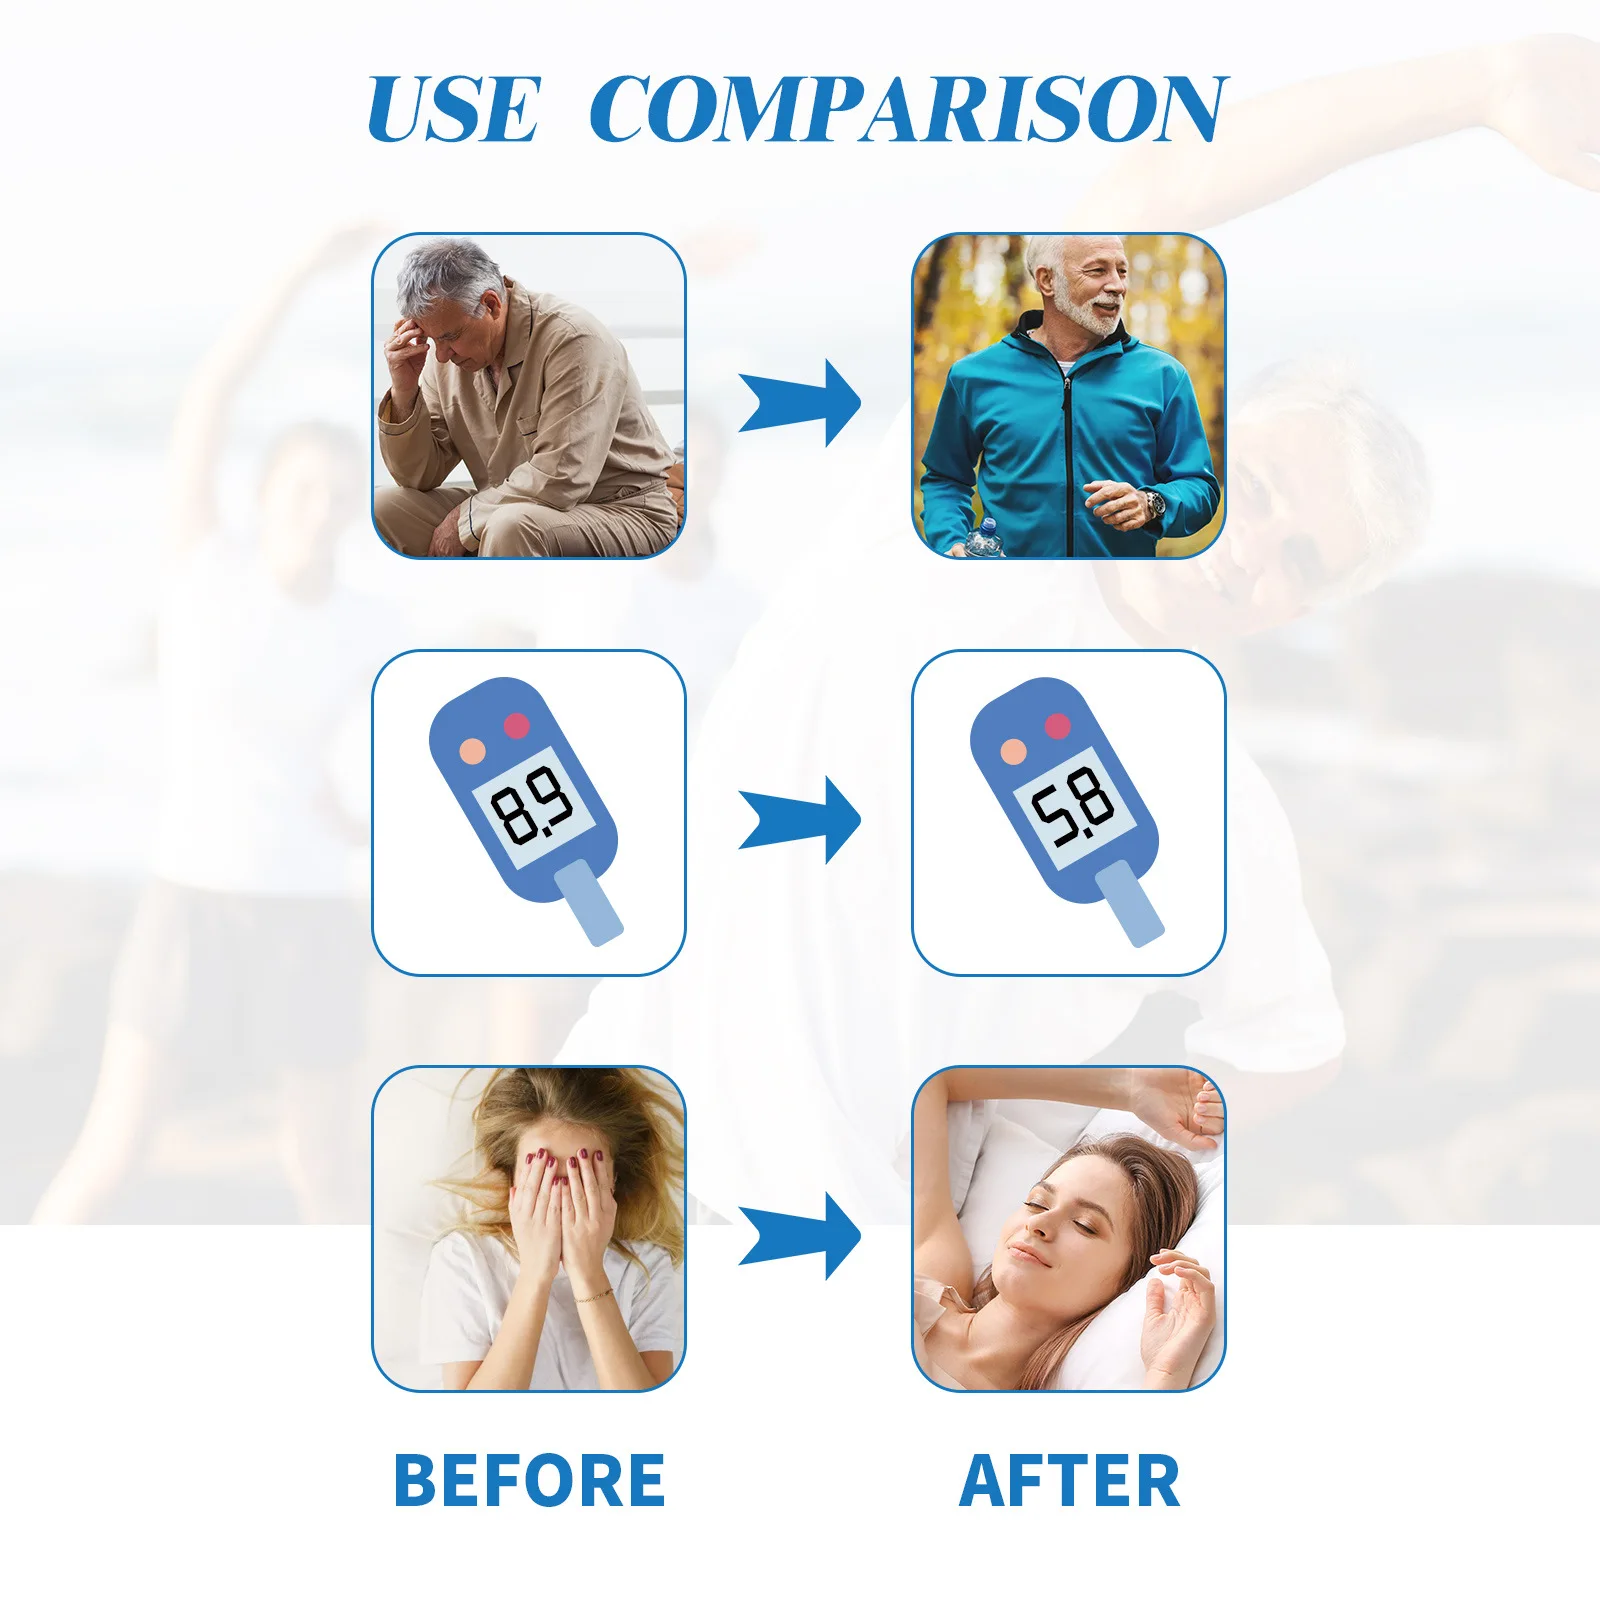

Effect: Sugar control

Model Number: Magnetic Control Blood Sugar

#Relieve Physical Discomfort Necklace

#Relief Nerve Pain Chain

#Relief Headaches Magnetic

#Relief Hyperglycemia Magnetic

#Healthy Energy Healing

#Health Necklace for Men